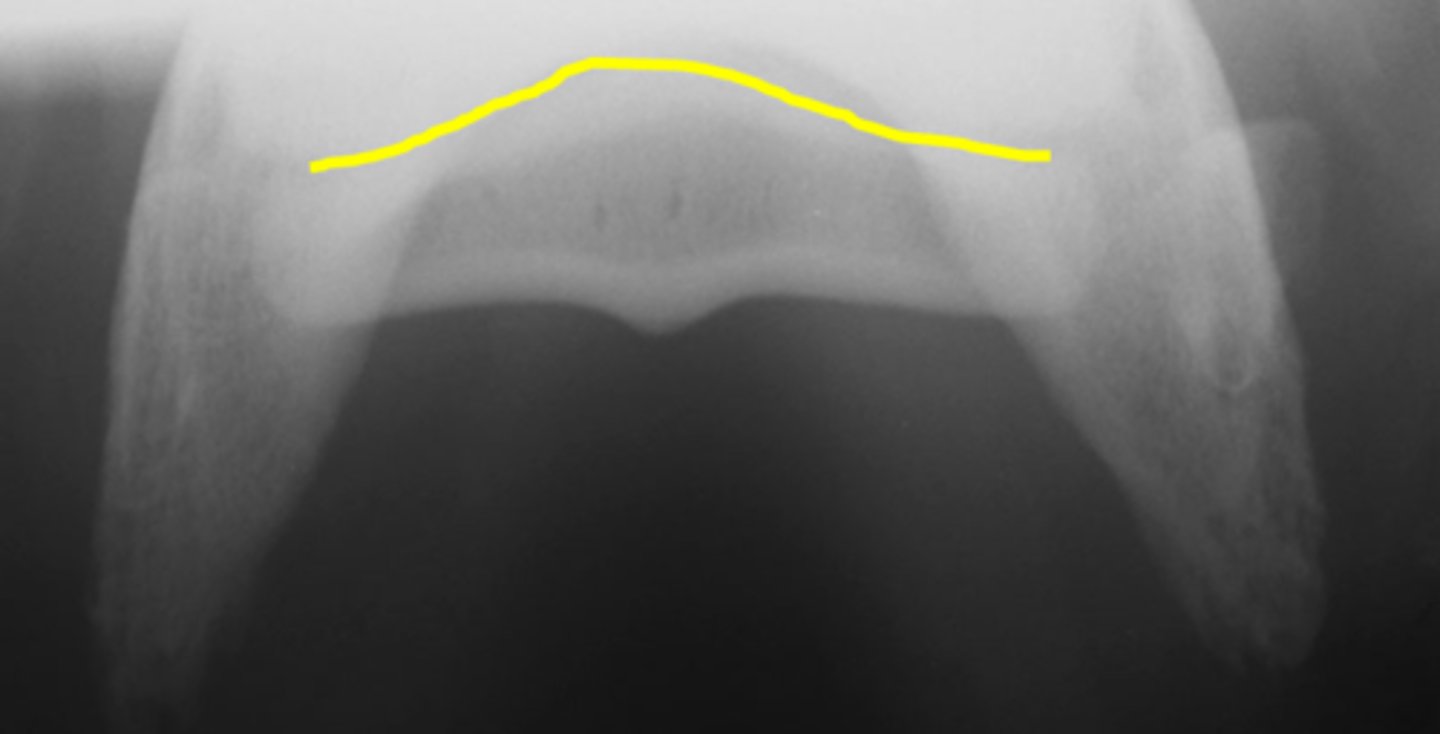

Flexor skyline

What view is this?

1. Flexor surface

2. Corticomedullary distinction

3. Number of synovial invaginations

What is the flexor skyline used to evaluate?